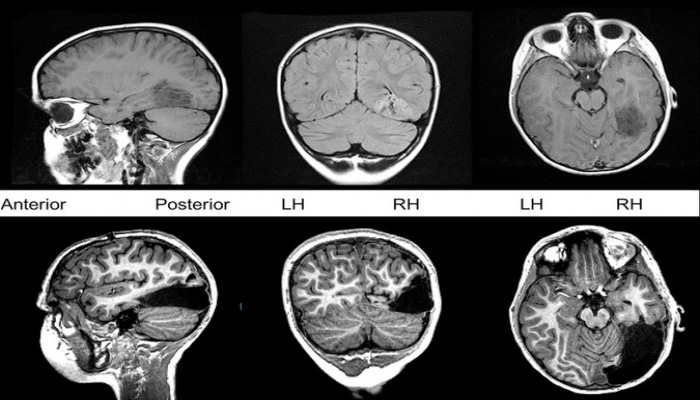

Qeyd edilir ki, adi şizofreniya xəstəsində sağlam insanla müqayisədə daha az beyin parçası müşahidə olunur. Yeni növ isə boz maddənin həcminə təsir etmir, onlar normal beyinlə oxşardır.

Bu xəstəlik 300 pasiyentdə beyinin analizi əsasında aşkarlanıb.